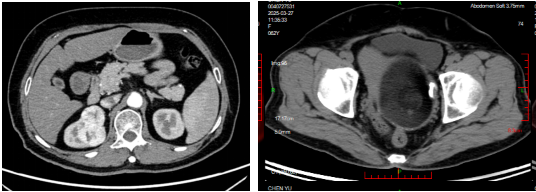

患者女性,63岁,因绝经后阴道出血在外院就诊,病理确诊为子宫内膜腺癌,拟行手术治疗,术前CT意外发现肾脏占位,考虑肿瘤。随后,患者来到华西天府医院就诊,行PET-CT检查发现右肾上极糖代谢轻度增高肿块,同时双肺多发磨玻璃样密度结节,医生初步考虑为肾癌以及原发性肺癌可能,经过肾脏穿刺病理确诊为确诊为肾透明细胞癌。患者5月14日入院,因病情涉及多系统肿瘤,手术需同时解决妇科与泌尿外科问题,且需评估肺部病灶性质,对术前规划、术中操作及术后管理提出极高要求。

5月16日,按照手术计划,泌尿外科团队先行完成腹腔镜下右肾部分切除术,妇科团队接力完成单孔腹腔镜下子宫内膜癌根治术,切除了子宫、双侧输卵管卵巢、前哨淋巴结,术中出血仅100ml。患者术后2天恢复自主活动,目前病情稳定,后续将继续跟踪患者肺结节情况。